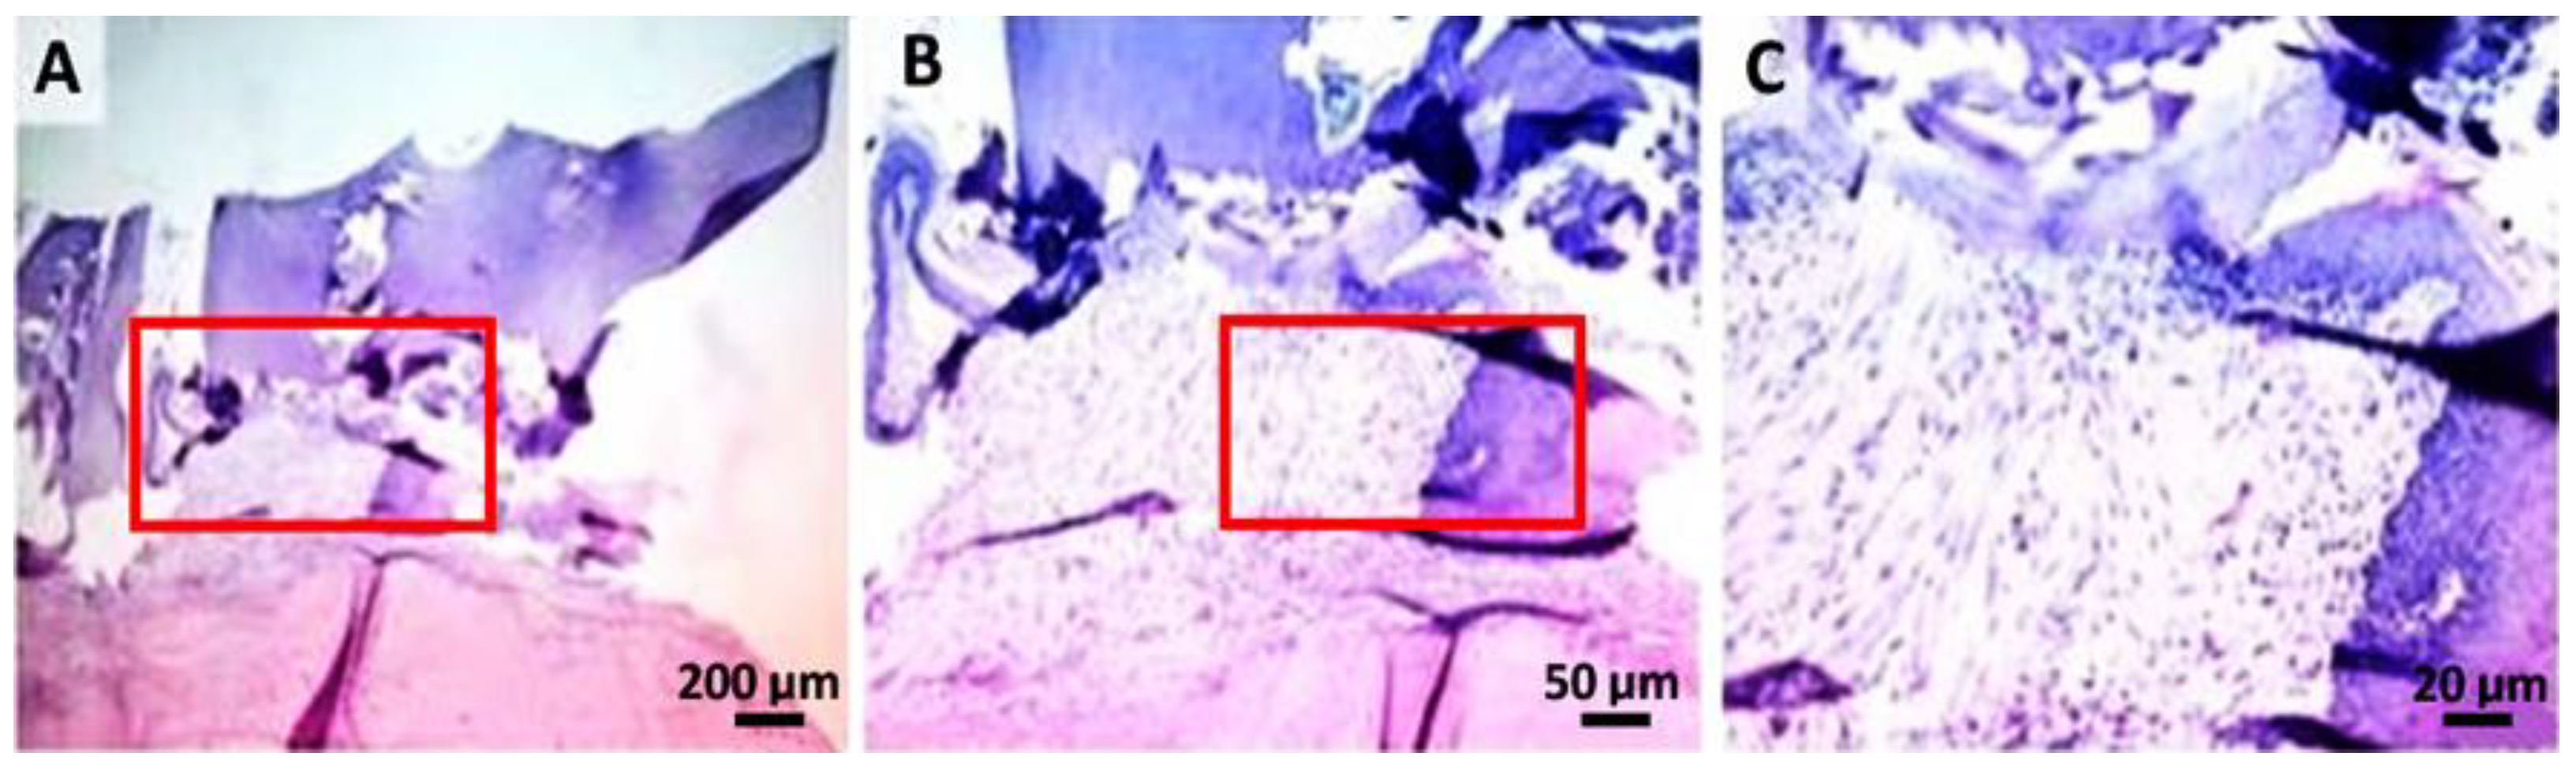

2.4. Histological Analysis

4.6. Histological Analysis